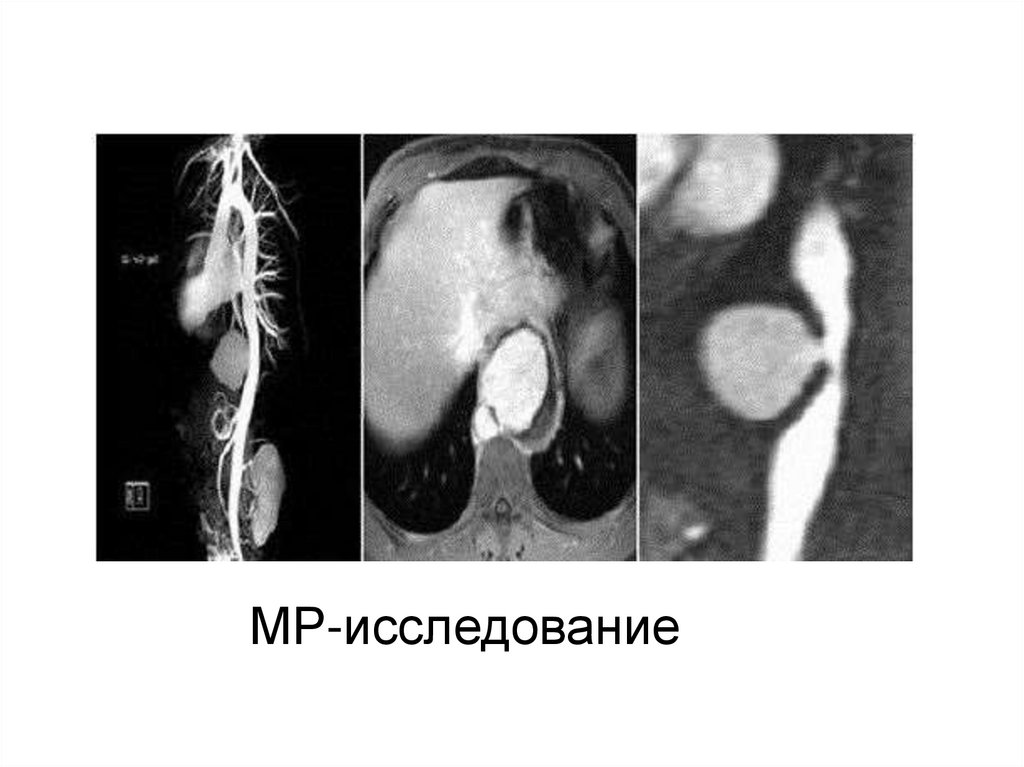

29. МР-исследование

30. Аортография